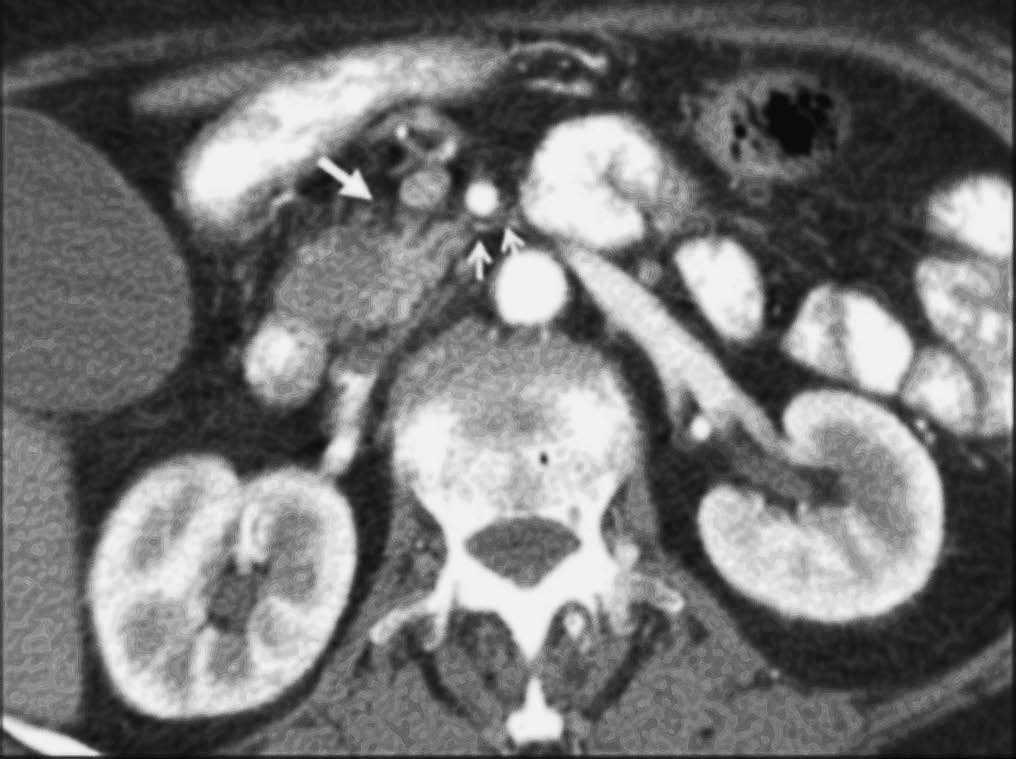

Aunque algunos autores no han observado diferencias significativas en cuanto al rendimiento de la TC helicoidal monofásica y bifásica en la detección y estadificación del cáncer de páncreas13, otros autores19,32, en series más largas incluyendo un mayor número de pacientes con tumores resecables, han aseverado el rendimiento de la TC helicoidal bifásica en la predicción de la resecabilidad del cáncer de páncreas, presentando valores predictivos para la resecabilidad tumoral entre 73,5% y 77% y valores de precisión diagnóstica entre 77% y 83%. Revisando específicamente los signos TC de infiltración vascular mediante TC helicoidal bifásica, Lu et al33, utilizando un sistema de gradación basado en la contigüidad del tumor con cada una de las estructuras vasculares (venas porta y mesentérica superior, o arterias hepática, mesentérica superior y tronco celíaco), presentaron un valor predictivo positivo del 95% y un valor predictivo negativo para la irresecabilidad neoplásica del 93% cuando consideraban infiltración vascular una contigüidad del tumor que excedía el 50% de la circunferencia del vaso en cuestión (fig. 4). A este mismo respecto Phoa et al34 describen como criterios de TC más fiables de invasión venosa la estenosis e irregularidad de la vena porta o la vena mesentérica superior, así como una contigüidad circunferencial del tumor con la vena porta superior a 90º (fig. 5). Los autores concluyen que la mejor combinación de criterios de TC fue la concavidad tumoral con afectación circunferencial vascular, con lo que presentan una sensibilidad del 61% y especificidad del 90%. Hough et al35 describieron el signo de la lágrima de la vena mesentérica superior, que consiste en una deformidad de la morfología redondeada de la vena adyacente al tumor en las secciones axiales, como indicativo de invasión venosa (fig. 6). Añadiendo este signo a los ya descritos de invasión venosa, consiguen aumentar la sensibilidad (60-91%) y el rendimiento diagnóstico de la TC (79-95%) sin modificar significativamente la especificidad (100-98%). No obstante, estos sistemas de gradación para el diagnóstico de la invasión vascular peripancreática tienen el inconveniente de la subjetividad a la que está sometida su lectura. Los casos extremos no presentan problemas de interpretación, pero la valoración del tumor rodeando al vaso alrededor de 90º de su circunferencia puede ser difícil, dado que además pueden existir bandas de infiltración de la grasa peripancreática que pueden rodear parcialmente un vaso o incluso continuarse sin plano graso de separación con el tejido tumoral. Estas bandas pueden representar cambios edematosos o inflamatorios locales (fig. 7). En este sentido, Valls et al19,36 presentan únicamente un 25% de valor predictivo positivo para la irresecabilidad tumoral para estas bandas perivasculares. Además se ha descrito la notoria variabilidad interobservador en función de su experiencia, que llega a alcanzar una diferencia de sensibilidad de hasta un 20% entre revisores experimentados y noveles14.

Fig. 5.--Adenocarcinoma de páncreas. Estudio de tomografía computarizada con contraste endovenoso en fase pancreatográfica. Masa de 5 cm al nivel de la cabeza pancreática que contacta ampliamente con la vena mesentérica superior (VMS) en aproximadamente 50° de su circunferencia, sin deformarla ni disminuirla de calibre. En la intervención quirúrgica se confirmó la invasión de la VMS, realizándose resección con interposición de injerto venoso.

Fig. 6.--Estudio de tomografía computarizada con contraste endovenoso en fase venosa portal. Infiltración vascular de la vena mesentérica superior. Signo de la lágrima: deformidad focal de la morfología de la vena en contigüidad con el tumor.